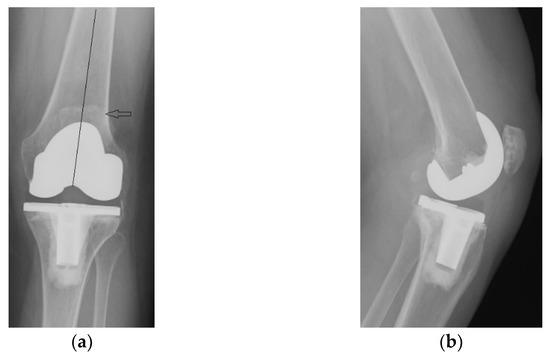

The immediate and distant postoperative evolution were favorable, as the radiological evaluation performed on the 2nd day after surgery shows; unfortunately, the lateral view is rotated (Figure 6).

Figure 6.

(a) Coronal view, patella centered on femoral axis (arrow); (b) Lateral view.

Radiological and clinical follow-up were performed at 6 weeks, 3 months and then 12 months after surgery (Figure 7, Figure 8 and Figure 9).

Figure 7.

Radiological imaging at 6 weeks after surgery: (a) Coronal view; (b) Lateral view.